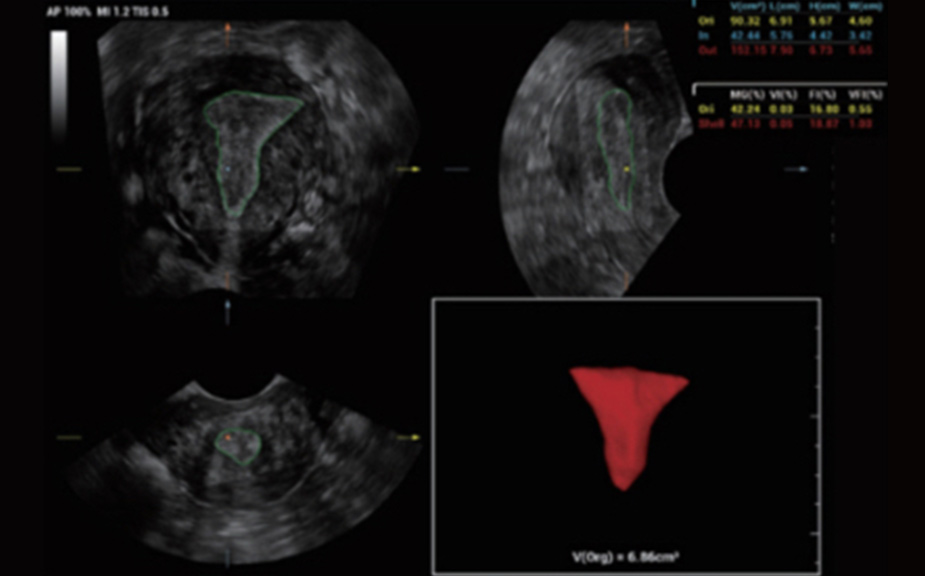

Scenario-oriented Full-stack Intelligence

The innovative Smart Scene 3D solution enables automated identification of tissue characteristics and delivers organ-specific diagnosis with full-stack intelligence throughout the entire procedure. This innovation reduces dependence on clinical skills, while elevating diagnostic accuracy, confidence, and efficiency.